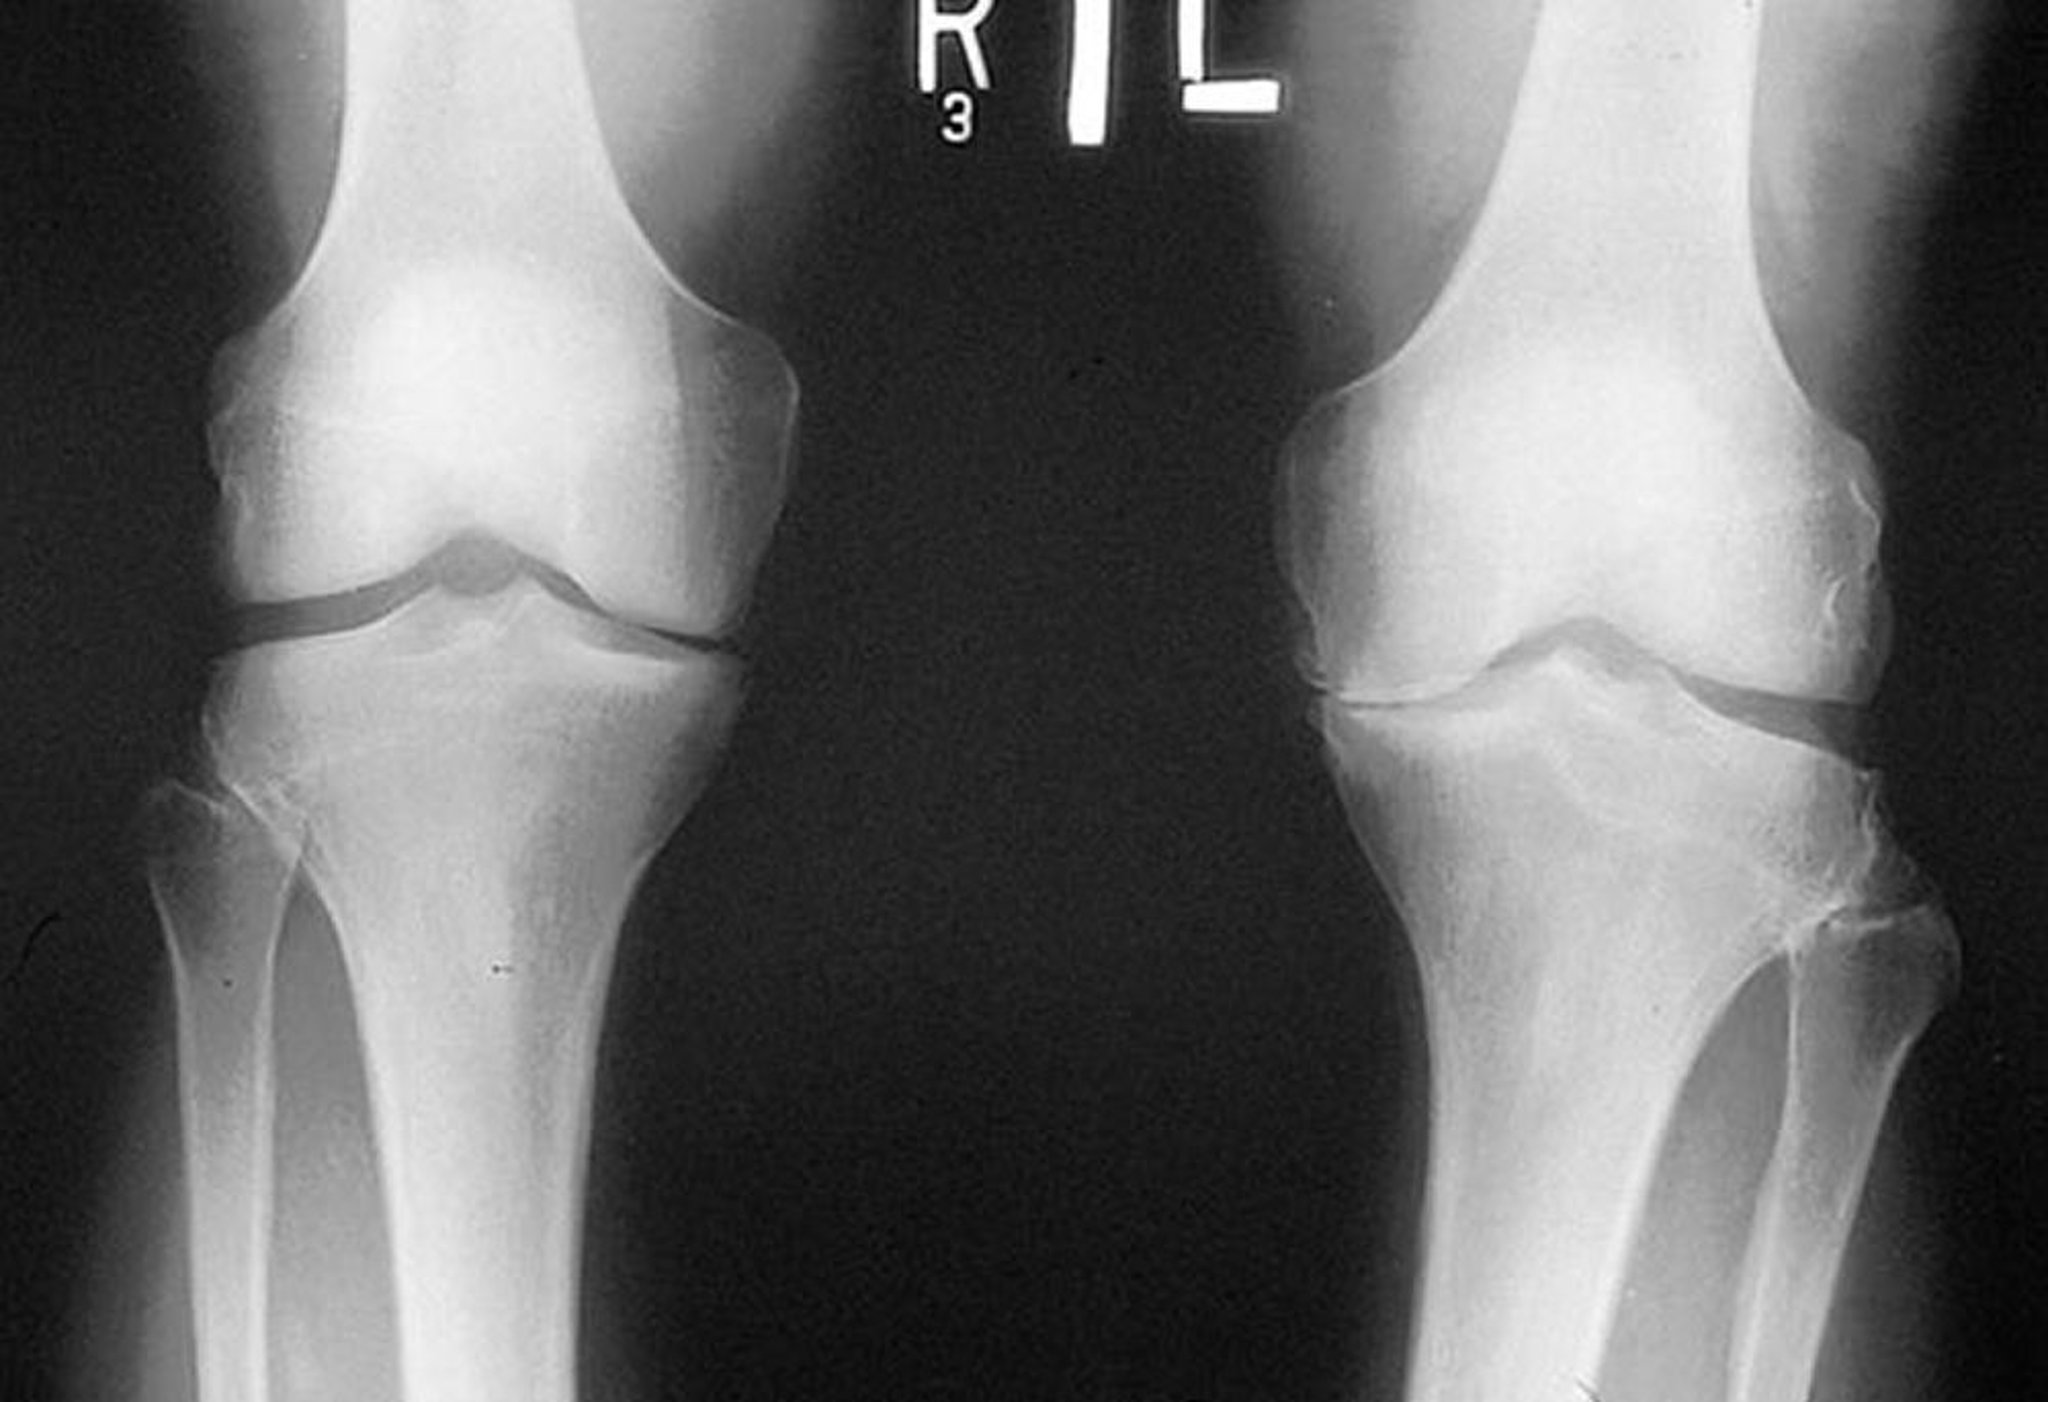

Рентгенологическое исследование коленного сустава при остеоартрозе

На рентгенограмме, сделанной в положении стоя, показано сужение большеберцово-бедренной суставной щели в медиальных отделах обоих колен, особенно слева. Определяются краевые костные разрастания. Истирание левой медиальной части плато большеберцовой кости.